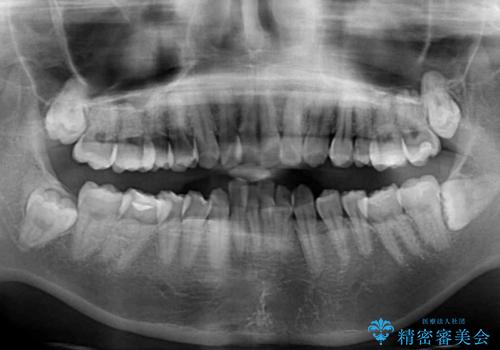

- 上の前歯の飛び出した感じと上下前歯のデコボコを気にして来院された患者様です。

叢生が強く、口元の突出感もあるため、上顎左右第一小臼歯4本を抜歯することとしました。

奥歯の咬み合わせ改善が必要なため、ワイヤー装置による矯正治療を強くお勧めしまたが、本人の希望でインビザラインにて治療を開始することとなりました。

インビザラインでの抜歯治療は予定通りに治療が進まないことが多いため、必要であればワイヤー矯正に切り替えるとお伝えした上で治療を開始しました。

2年ほどインビザラインを使用しましたが、どうしても歯の移動がマウスピースに追随せず、全顎ワイヤー矯正へ切り替えました。